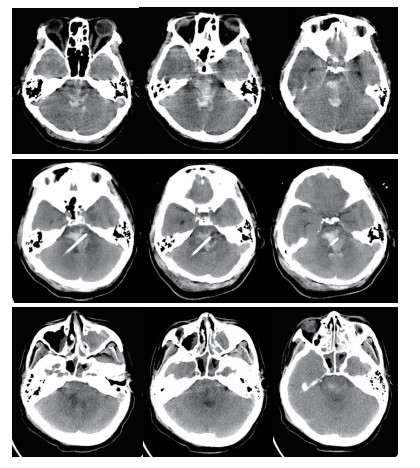

穿刺路径选择:行脑干出血立体定向穿刺分别采用幕上经额部及幕下经桥臂两种入路,笔者根据血肿的位置及患者的病情选择相应的入路,经幕上穿刺尤其适合侵及中脑的血肿,优点:体位摆放方便,对患者呼吸功能影响小,操作较简便,手术时间较短,血压监测较方便。缺点:穿刺路径较长,可能穿过脑室造成引流管移位,穿过丘脑及中脑,损伤损伤丘脑及中脑结构,如引流管置入过深可能损伤延髓。经幕下穿刺优点:经桥臂穿刺,穿刺路径短,损伤重要结构少,缺点:手术中需要侧卧位,可能影响呼吸,手术前应行气管插管,上头架时应预留手术穿刺位置,及耳环的位置,体位摆放及术中操作较复杂,手术时间较长。对于血肿侵及中脑或病情较重的患者,一般选择幕上经额穿刺(图 1)。如患者病情允许或术前有脑积水的患者,一般选择经幕下经桥臂入路,并根据血肿形态使引流管纵行穿过血肿(图 2)。

| 图 2 经幕下入路脑干血肿穿刺A:血肿穿刺前B:血肿穿刺后复查C:穿刺后6 d复查 |

本组手术术后24 h内血肿大部排空有7例,24~48 h大部排空有11例,48~72 h大部排空8例(图 1,2)。于1~4 d内拔除血肿腔引流管。术后8例患者3个月内死亡,死亡率25.8%。1例术中突发血压持续降低后,术后弥漫性脑肿胀死亡。1例术前吸入性肺炎严重,术后感染性休克死亡。1例肝功能不全,术中术后反复出血,家属放弃治疗死亡。1例术后不明原因高热,消化道出血,家属放弃治疗死亡。2例术后突发呼吸心搏骤停死亡。2例术后再出血,家属放弃治疗死亡。18例于术后3个月内清醒,均留有不同程度残疾,5例3个月内未清醒,存活病例随访3个月至1年后,格拉斯哥结局量表(GOS) 5级5例,4级7例,3级6例,2级5例,1级8例。植物状态及死亡患者多为出血量大(>10 mL),术前昏迷程度较深的患者(GCS评分3~5分)。